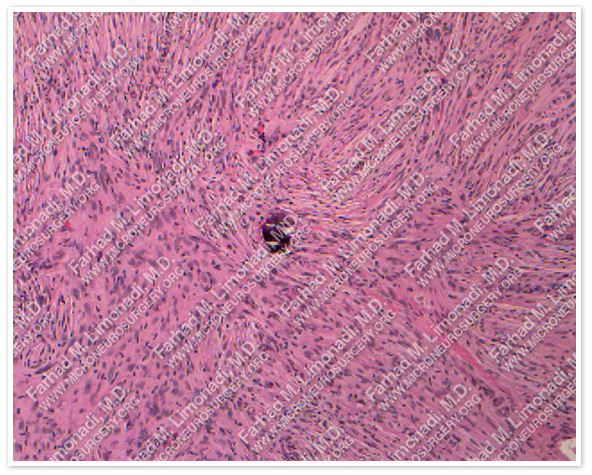

Pathology

The pathology of the tumor confirmed diagnosis of meningioma.